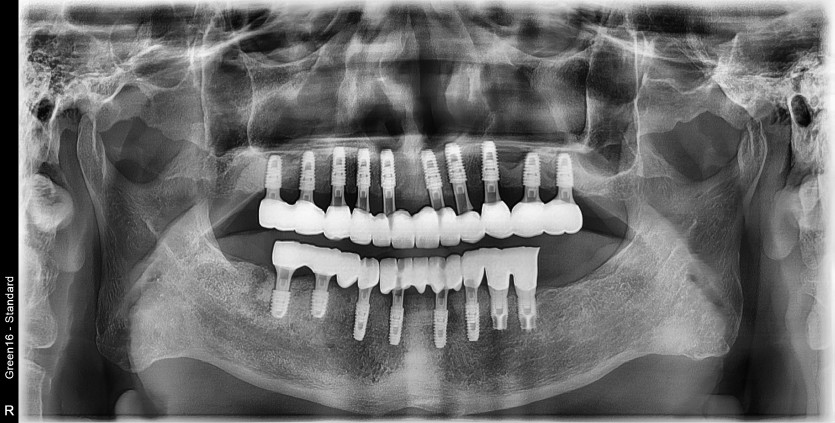

전체 임플란트 증례입니다.

16개의 임플란트로 완성하였습니다.